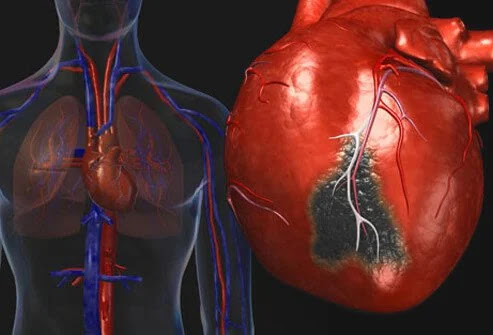

Όταν μια στεφανιαία αρτηρία μπλοκάρει (συνήθως από έναν θρόμβο αίματος), μια περιοχή του καρδιακού ιστού χάνει την παροχή αίματος. Αυτή η μείωση του αίματος μπορεί να βλάψει γρήγορα ή/και να σκοτώσει τον καρδιακό ιστό, επομένως είναι απαραίτητες γρήγορες θεραπείες στο τμήμα επειγόντων περιστατικών και/ή καρδιακό καθετηριασμό για να μειωθεί η απώλεια καρδιακού ιστού.

Η απώλεια ιστού της καρδιάς λόγω απόφραξης μπορεί να προκαλέσει συμπτώματα όπως πόνο στο στήθος, δύσπνοια, αδυναμία, ακόμη και θάνατο.

Πώς η πλάκα, οι θρόμβοι αίματος μπορούν να προκαλέσουν καρδιακή προσβολή

Οι ρήξεις πλακών μπορεί να προκαλέσουν το σχηματισμό θρόμβων που εμποδίζουν την αρτηριακή ροή αίματος.

Η πλάκα μπορεί να εμφανιστεί στις στεφανιαίες και άλλες αρτηρίες (για παράδειγμα, στις καρωτιδικές αρτηρίες). Κάποια πλάκα μπορεί να είναι σκληρή ή σταθερή εξωτερικά, αλλά μαλακή και αφρώδης ή κολλώδης στο εσωτερικό. Εάν ανοίξει η σκληρή περιοχή που μοιάζει με κέλυφος, συστατικά αίματος όπως τα αιμοπετάλια και οι μικροί θρόμβοι σχηματίζουν έναν μεγάλο θρόμβο και εμποδίζουν αποτελεσματικά τη ροή του αίματος μέσω της αρτηρίας. Ο καρδιακός ιστός βρίσκεται χαμηλότερα από τον θρόμβο στη συνέχεια, υποφέρει από έλλειψη αίματος και καταστρέφεται ή πεθαίνει.